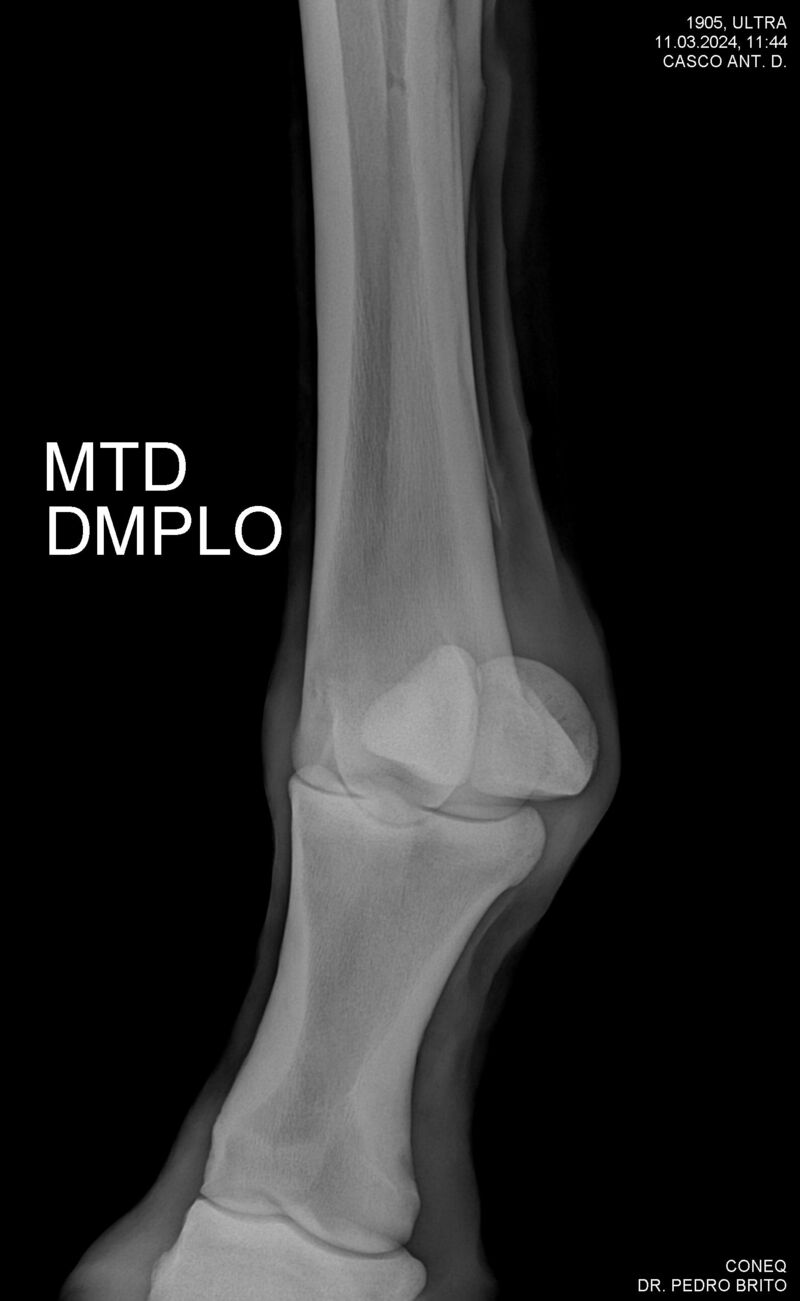

ULTRA DO CACH

Raça: BRASILEIRO DE HIPISMO

Sexo: CASTRADO - CASTRADO

Nascimento: 22/11/2020

Altura Aproximada: 1,67

Pel.: CASTANHO

Registro: 25966-BH

Vend.: HARAS CACHOEIRINHA

Local : PIRASSUNUNGA/SP